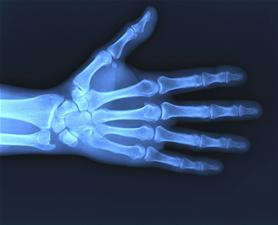

Prawidłowa struktura kości jest wypadkową aktywności dwóch typów komórek. Pierwsze to osteoblasty, tworzą one mineralne rusztowanie kości. Drugi typ to osteoklasty. Komórki te odpowiadają za resorpcję kości, czyli wchłaniają kości, są komórkami żernymi. Równowaga pomiędzy przeciwstawnymi aktywnościami tych dwóch typów komórek podlega regulacji przez hormony, neurotransmitery i cytokiny.

Jak wyjaśnia Urszula Kędzierska, główna cytokina prozapalna - czynnik martwicy nowotworów - wpływa stymulująco na aktywność osteoklastów i hamuje aktywność osteoblastów. Dlatego zmniejszenie gęstości mineralnej kości, prowadzące do osteoporozy jest częstym zjawiskiem towarzyszącym przewlekłym stanom

zapalnym.